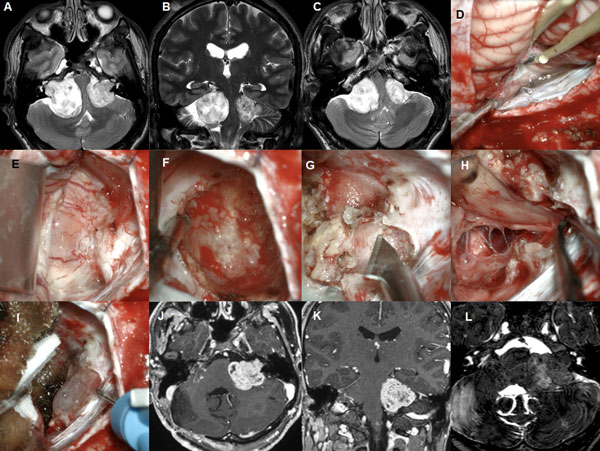

Figura 7: Paciente masculino de 37 años, operado de SV T4b derecho con quiste externo. A-C: RM cerebral preoperatoria. D-J: imágenes intraoperatorias, K-L: RM cerebral postoperatoria

Figura 8: Paciente masculino de 62 años, operado de SV T4b multiquístico. A-B: RM preoperatoria. C-D: RM cerebral postoperatoria.